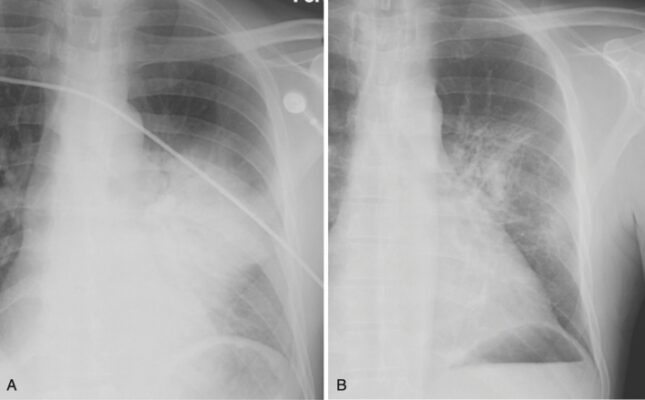

- Điển hình biểu hiện là một viêm phổi kẽ dạng lưới, quanh rốn phổi hoặc như một bệnh khoảng chứa khí có thể trông giống như dạng phân bố trung tâm của phù phổi (Hình 5).

- Các biểu hiện khác, chẳng hạn như bệnh khoảng chứa khí một bên hoặc bệnh khoảng chứa khí loang lổ ít phổ biến hơn.

- Thường không có tràn dịch màng phổi và không có hạch rốn phổi

- Nhiễm trùng cơ hội thường xảy ra khi lượng CD4 dưới 200 / mm máu.